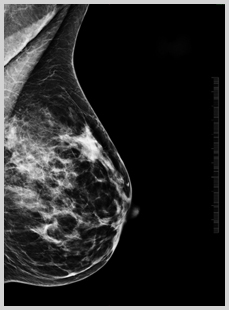

Κάνε μαστογραφία! Η μαστογραφία είναι η πιο αποτελεσματική μέθοδος για να ανακαλύψεις έγκαιρα τον καρκίνο του μαστού.

Η μαστογραφία (μια ειδική ακτινογραφία) μπορεί να ανιχνεύσει κάποιο ογκίδιο πολύ πριν να

μπορέσει να ψηλαφηθεί με το χέρι. Μια πρώτη μαστογραφία πρέπει να γίνεται ανάμεσα στην ηλικία των 35-39, η οποία θα χρησιμοποιηθεί για σύγκριση για οποιαδήποτε αλλαγή στο στήθος αργότερα.

Από την ηλικία των 40 ετών και μετά θα πρέπει να επαναλαμβάνεται κάθε 1 με 2 χρόνια, εκτός αν ο γιατρός σού προτείνει κάτι άλλο. Η μαστογραφία θα πρέπει να γίνεται την εβδομάδα μετά την περίοδό σου. Μερικές γυναίκες μπορεί να χρειαστεί μετά τη μαστογραφία να κάνουν κι ένα υπερηχογράφημα, εάν το στήθος τους έχει πολύ πυκνό ιστό.